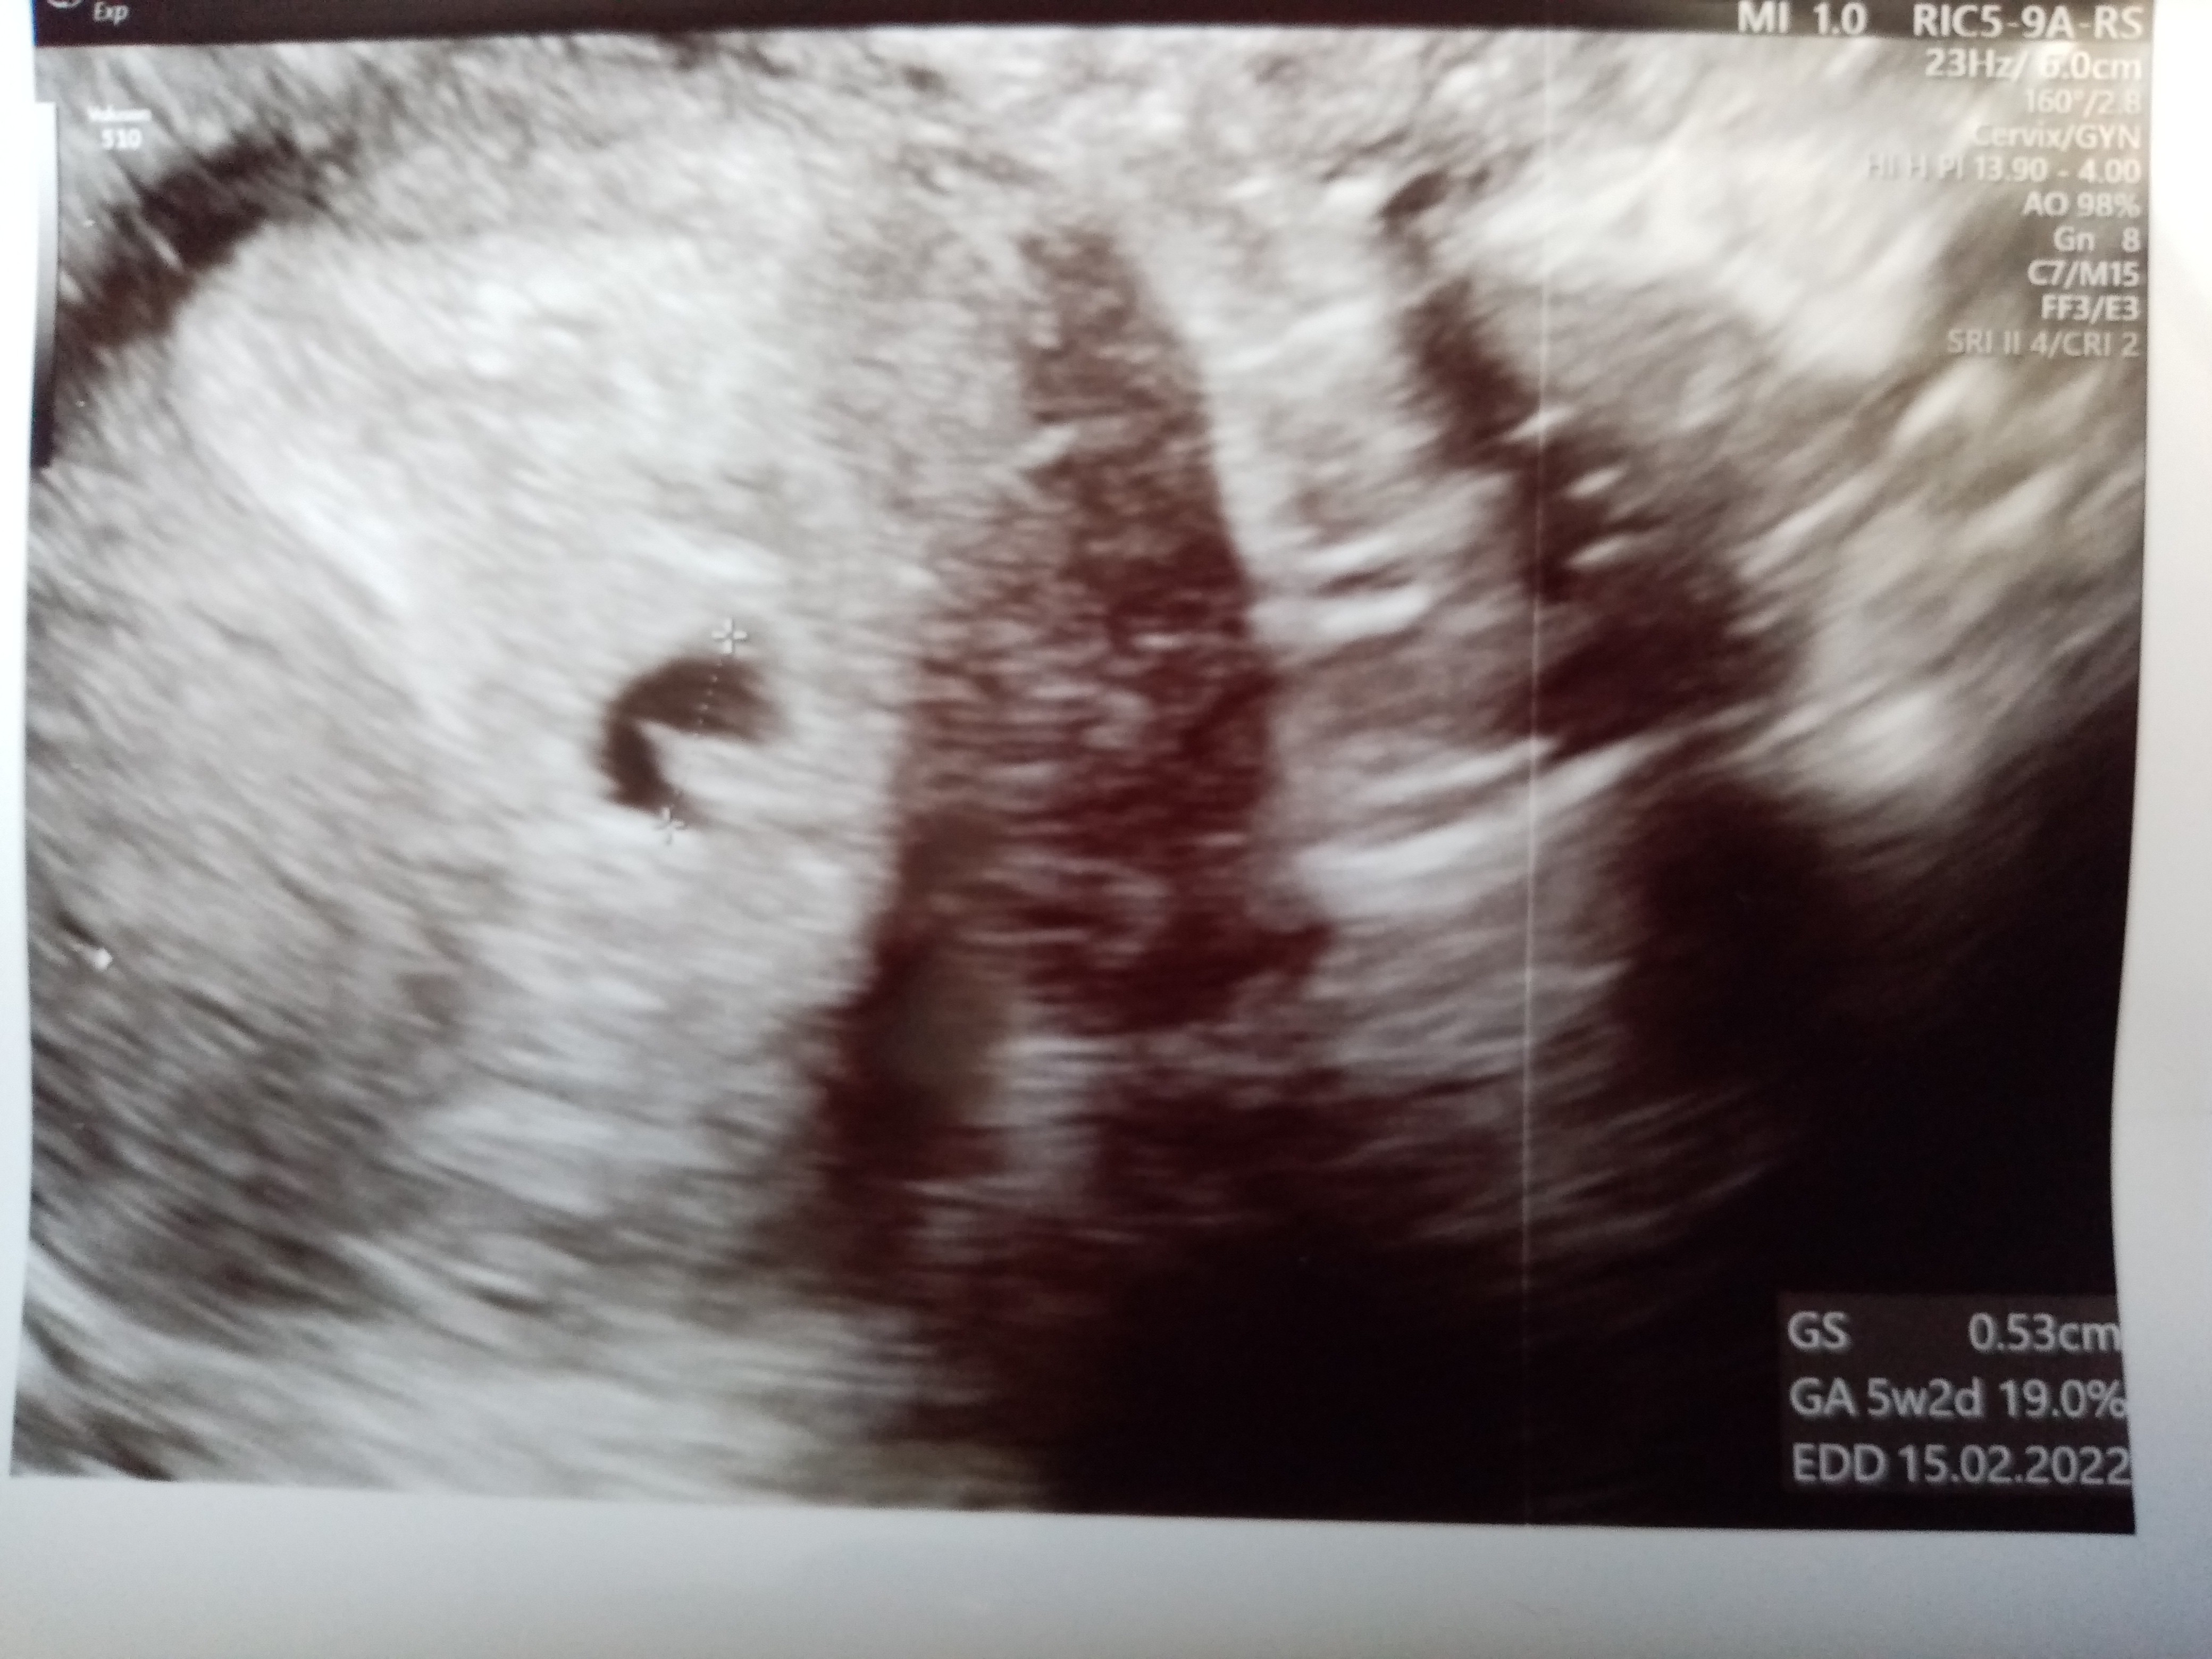

Dziewczyny byłam dzisiaj prywatnie na wizycie. Pęcherzyk jest w macicy i większy niż 2 dni temu ale bez ciałka żółtego . Ma 5mm. Jutro wyniki bety i progesteronu. Wklejam zdjęcia. Co sądzicie?